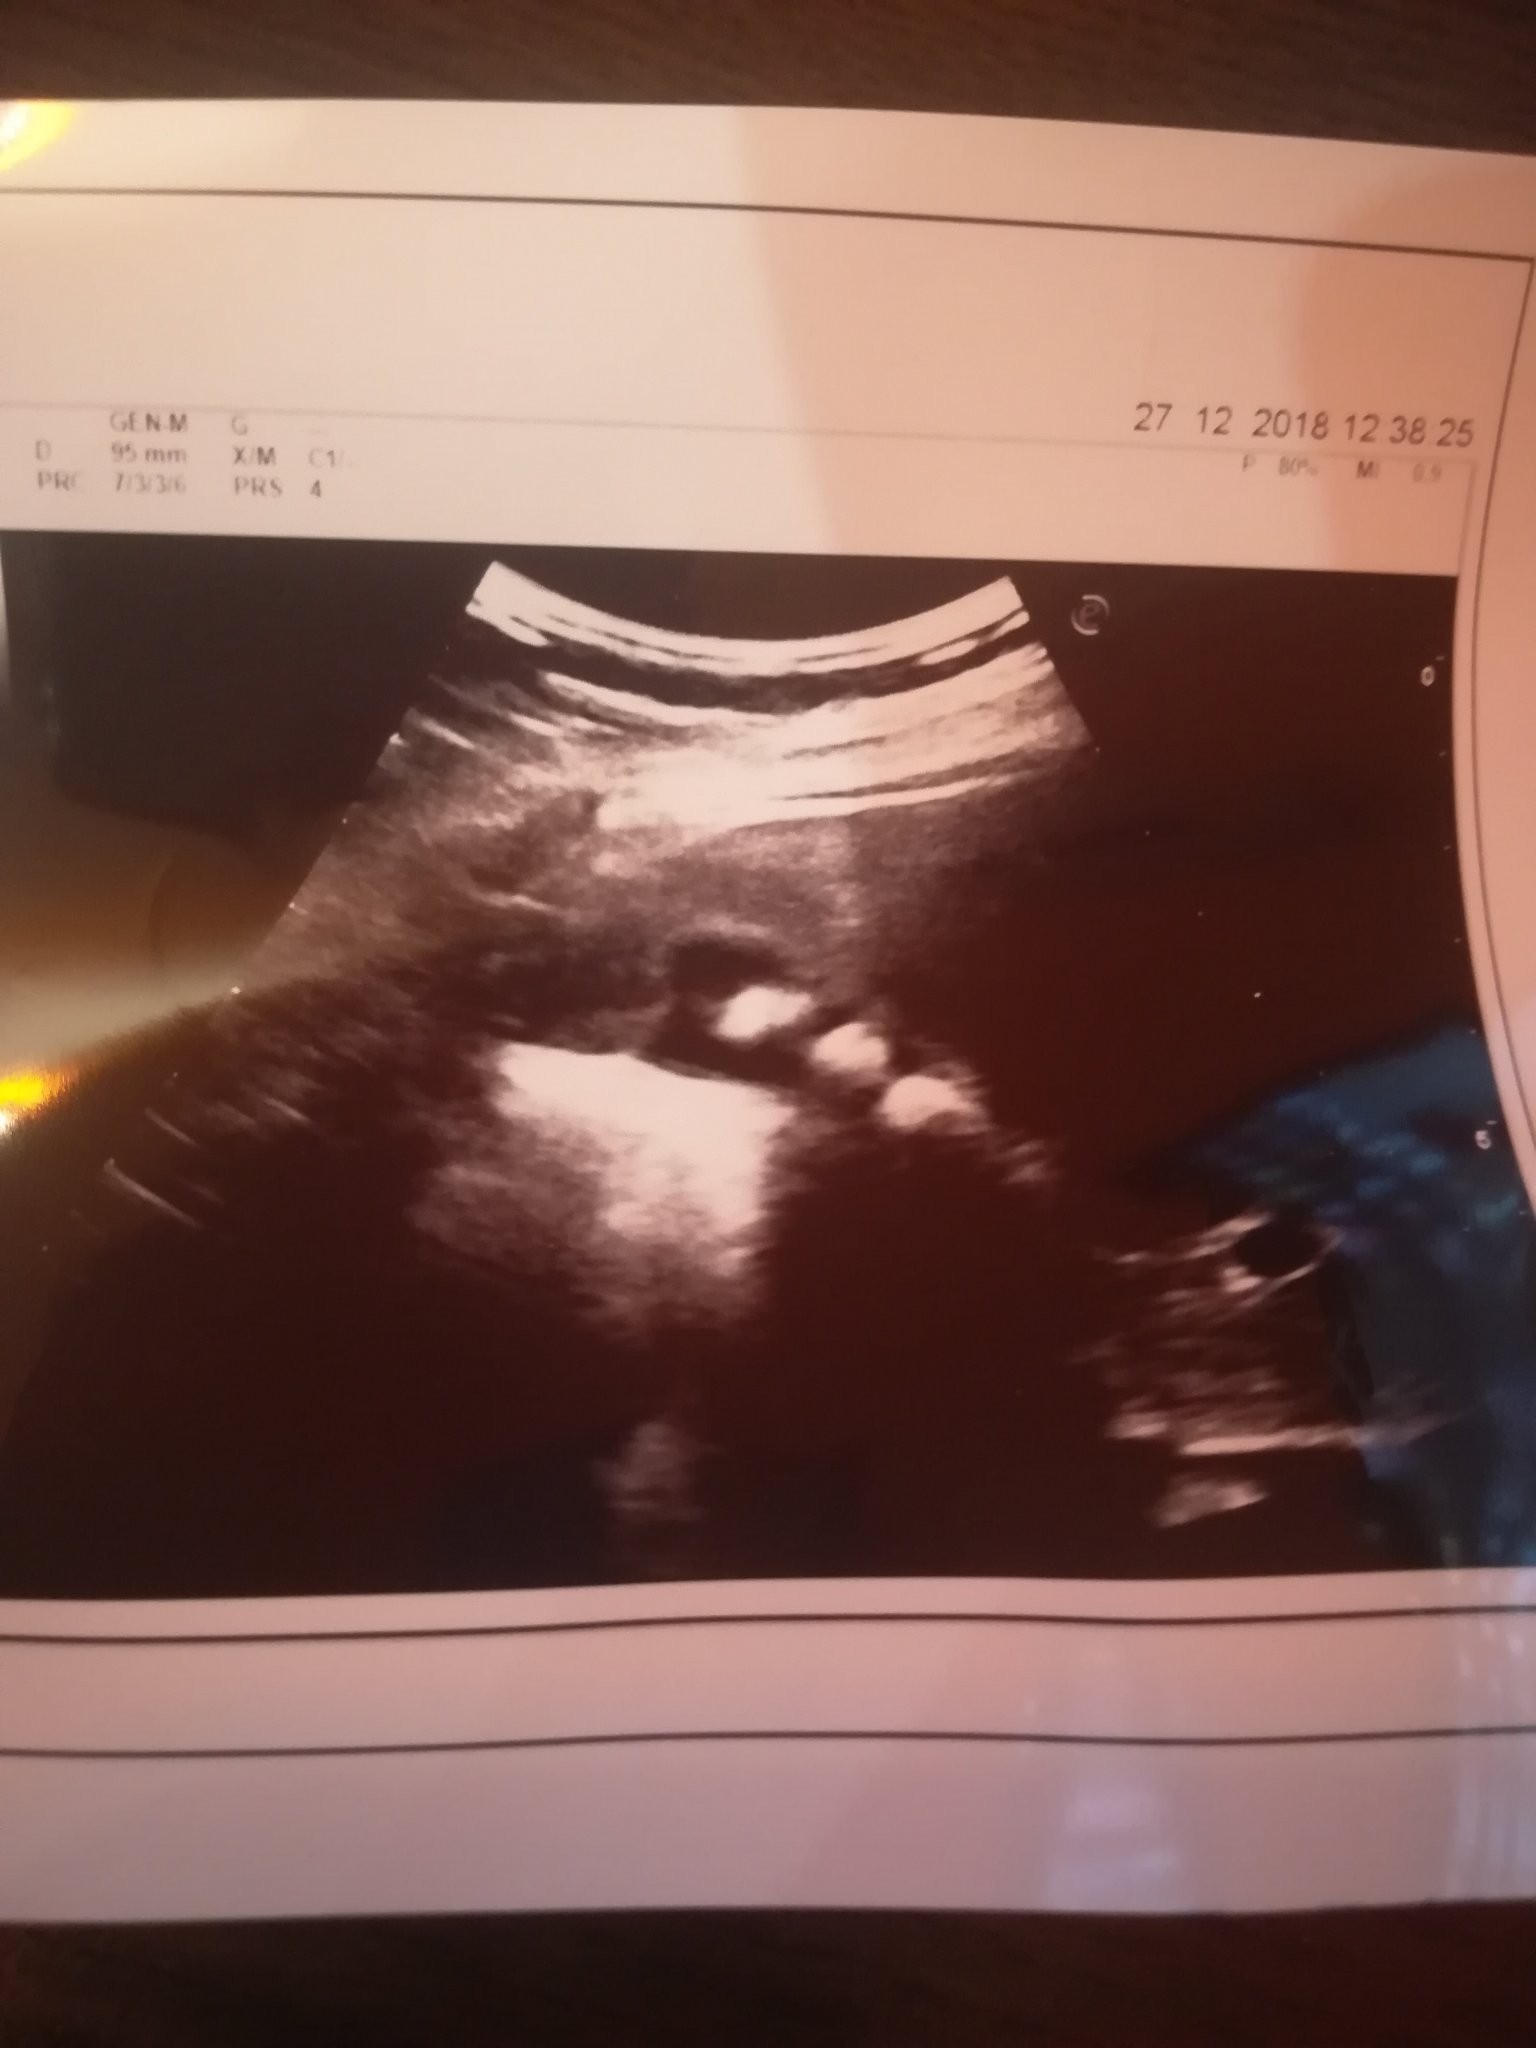

Точно така беше и при мен. Докато този декември не започна да боли всеки ден / пак там горе в средата/. Минаха няколко седмици и се изплаших да не е нещо по-страшно. Отидох на гастро и при прегледа на ехографа се видяха 3 камъни, ясно като бял ден. Веднага ми препоръча операция, но понеже беше между Коледа и Нова година, ми пусна изследвания да види колко е спешно. Всичко ми беше в норма и ми каза да си изкарам нова година, но да помисля за операция. След НГ се обадих в Токуда и си записах час за преглед за 15.02 и насрочих операцията за 14.03. Ето и моята снимка: